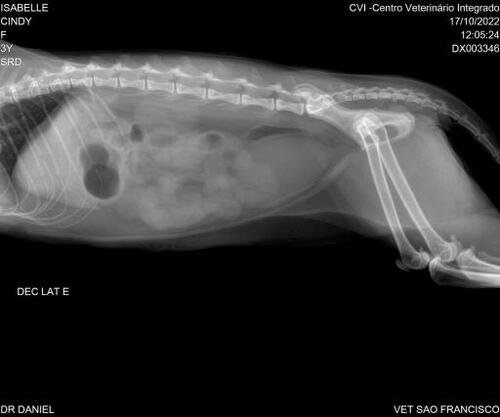

Foi detectado gastrite, inflamação na bexiga e com suspeita de corpo estranho linear no meu corpinho.

2. Recibo da internação e raio-x prévia

3. Minha Raio-x